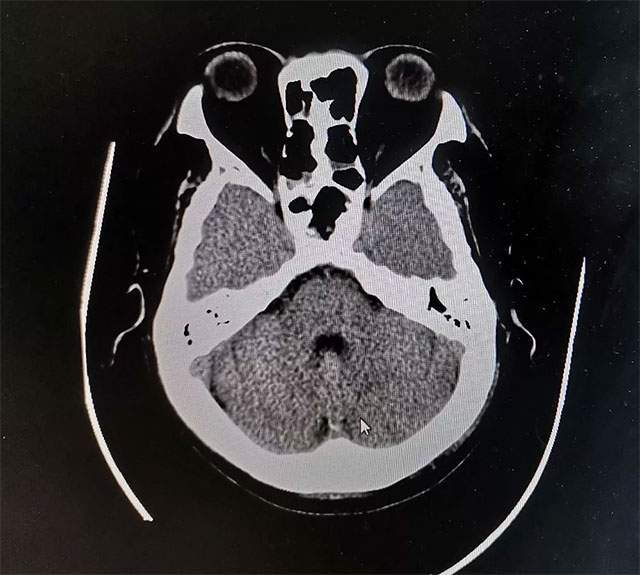

潘仁龙主任指出,CT在垂体卒中急性期平扫时即可见瘤内的高密度影出血灶,很容易辨别,但当进入亚急性期后则呈等密度,难于鉴别。因此,在高度怀疑垂体卒中的病例中应首选MRI扫描。此外,MRI 还能提供较 CT 更为清晰的三维空间解剖结构,它对肿瘤以及瘤体与周边正常组织的关系都可起到良好的显示作用。因此MRI是垂体瘤卒中的首选影像学检查手段,而在急性期,尤其是超急性期则首选CT。

▲ 术后影像显示肿瘤被切除